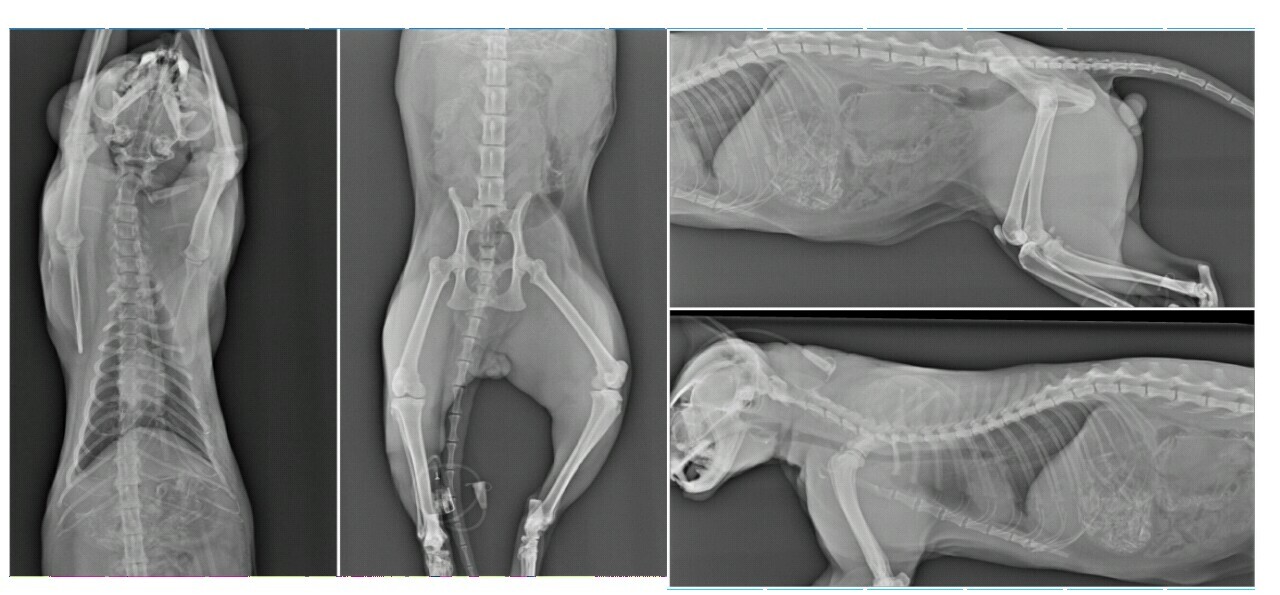

醫院中午打了好幾通電話給我,我忙到不知道要接,直到晚上忙完了,我見到多通未接來電才趕緊回撥,醫生說牠中午就離開了,主因是失溫,體溫過低,此外血檢多項指數都不樂觀(貓咪在接受各項檢查的過程中離開了,血檢報告是之後才出爐的),X光未發現骨折,只能推測可能有內出血。